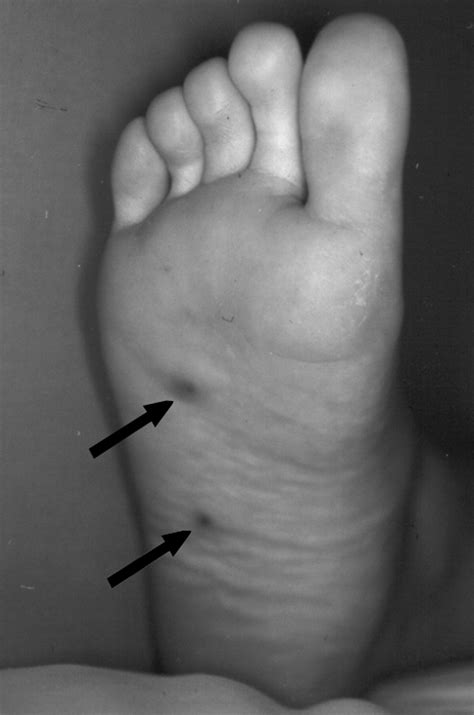

The primary symptom of a Blue Bleb Nevus is its distinctive appearance. These nevi are usually flat or slightly raised and have a blue or bluish-gray color. The blebs or blisters can be small or large and may rupture, leading to temporary changes in the appearance of the nevus. The nevi can occur anywhere on the body but are most commonly found on the trunk and extremities.

A Blue Bleb Nevus is a type of congenital melanocytic nevus characterized by its blue color and the presence of blebs or blisters. These nevi are typically present at birth or appear shortly thereafter. The blue color is due to the Tyndall effect, where light is scattered by the melanin in the deeper layers of the skin, giving it a bluish hue. The blebs are fluid-filled blisters that can vary in size and number.